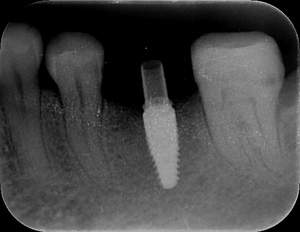

レントゲン写真

- Befor

- After

| 年齢 | 50代・男性 |

| 主訴 | 左下7番 |

| 治療内容 | 右下7番インプラント埋入 |

| 治療費 | 合計:572,000円 診断料:55,000円 埋入料:165,000円 サージカルガイド:55,000円 静脈内鎮静麻酔:77,000円 仮歯:55,000円 上部構造(フルジルコニア):165,000円 (2023年1月現在) |

| 治療期間 | 約8ヶ月 |

| 治療方針 | 骨が十分にあるため、骨造成をすることなく埋入した。かみ合わせが強いので、負荷がかからないよう、夜寝るときにマウスピースをつけるよう指示をした。 |

| 担当者所見 | 左下6番7番のインプラントは他院で埋入しており、右下7番は抜歯したままで、かみ合わせの歯が落ちてきてしまうのでインプラントを埋入しました。 |